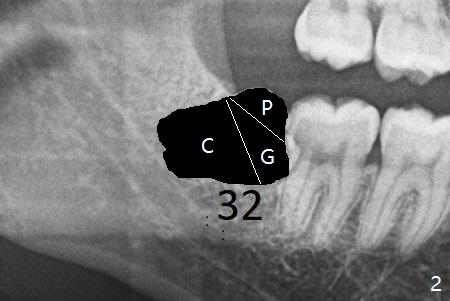

A 28-year-old woman returns for #17 and 32 extraction. To obtain full potential of bone regeneration after extraction, 3 D Bond (Graft Binder Cement, .5 cc, Fig.2 C) will be placed in the root portion of the socket of #32 , while allograft (G) and Collagen Plug (P) in the coronal one. For comparison, Osteogen Plug (Fig.3 O) will be inserted in the root portion of the socket of #17, while the other two materials same as those at #32. Take postop panoramic bitewing if both teeth are extracted. Otherwise take PA. Place the latter in the center of the extraction socket.

In fact the tooth #32 is extracted first; the defect involves the distobuccal aspect of the tooth #31 (Fig.4 *). An intraop PA is taken after extraction to confirm whether a broken surgical fissure bur tip retains or not; the distal lamina dura of #31 is low (Fig.5 *). It is expected to increase after cocktail bone graft (Fig.5' arrow). As planned, the bone cement (Fig.6 C) and allograft (G) are placed in the distal and mesial portions of the socket; between them is Osteogen Plug (O). Another piece of Osteogen Plug (as collagen membrane for bone graft) is placed on the top of the socket before suturing with 4-0 Plain Gut (Fig.7,7' O). Also note the bone graft being placed distobuccal (CT study) to #31 (Fig.7' red dashed line) to reduce possibility of future periodontitis. The patient returns 15 days postop with chief complaint of mild pain since extraction, although the wound looks normal. The transverse cortex connecting to the lamina dura (Fig.5 *) is obliterated when allograft is placed (Fig.7 G). The part of the graft remains in place 1 month postop (Fig.9) in spite of wound dehiscence (Fig.8). The bone graft loss is indicated by the fact of the reappearance of the transverse cortex (Fig.9). In the same appointment, the tooth #17 (Fig.10) is being extracted (Fig.11), leaving a defect mesiobuccal (Fig.12 *) to distal (curette). Part of Osteogen plug (Fig.13 O) is stretched to cover the mesially placed allograft (Fig.14 G). One quarter of Collagen plug is placed over the Osteogen plug (Fig.13 O) before 4-0 PGA suturing. There is bone regeneration 1 year postop (Fig.15,16).